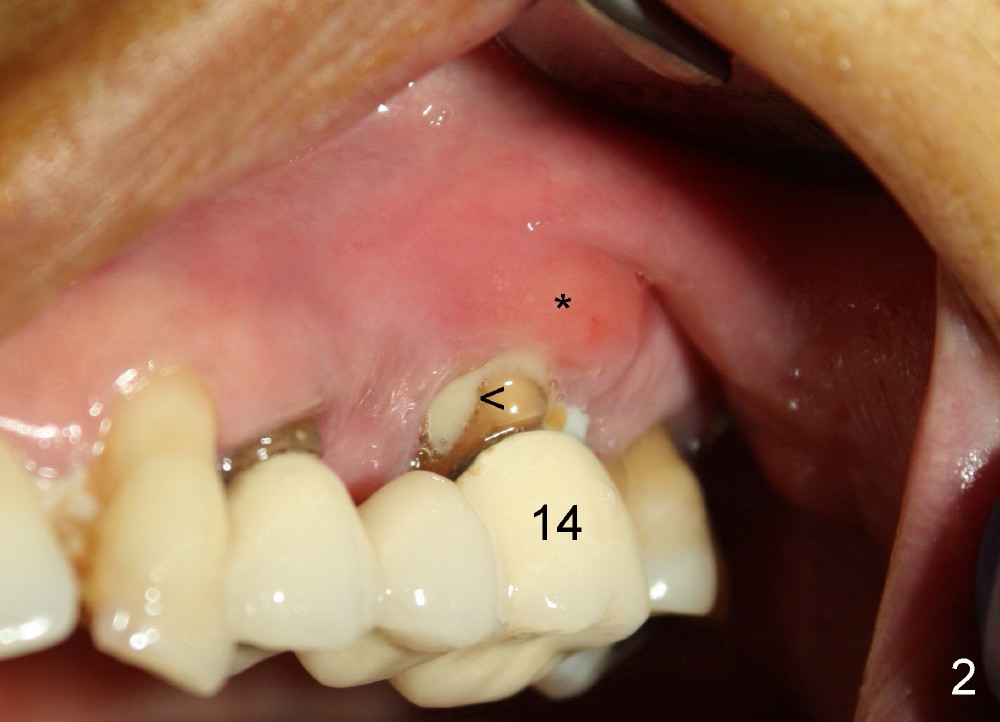

A 53-year-old lady has a failing bridge (Fig.1). There is severe bone loss around the buccal roots of #14 (*). Purulent discharge is from the gingival sulcus (Fig.2 <) with localized gingival erythema and edema (*). When the bridge is removed, the tooth #12 is found nonsalvageable (Fig.3,4). These two teeth are to be replaced by immediate implants (Fig.5). Although the sinus floor is low buccally (arrowheads), a 6x14 mm gingiva-level implant can be placed in the septum close to the palatal socket or in the palatal socket at the site of #14.